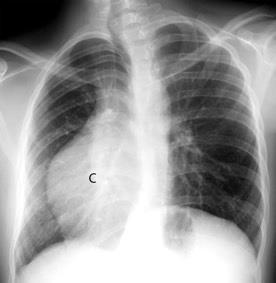

Tumor desmoide derecho. Recidiva.

Tumor maligno. 0,2% de los tumores de mama.

Ocurren en 10% de los implantes de mama.

En los 3 años después del implante.

(Dudas sobre el dato)

Kilmartin C et al. Desmoid Tumor and Implant-Based Breast Reconstruction. Case Rep Oncol. 2023